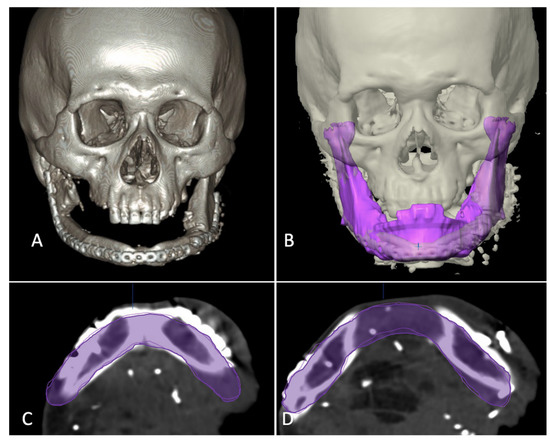

Category I included the cases where the reconstruction defect did not cross the midline. ‘Mirroring’ function integrated in the software was used to obtain the template of the defect from the normal sided mandible and whole mandible could be virtually constructed. Since the position of residual mandible is distorted in most of cases of secondary reconstructions, the residual mandible was also realigned to near-original position, taking occlusal relation as a guide and then mirroring it (Figure 2).

Figure 2.

Designing template in category I. (A) 3-dimensional view of defect. (B) Segmentation of right hemimandible (blue color). (C) Mirroring to the left side (pink color). (D) Merging both sides to form simulated whole mandible for printing (yellow color).